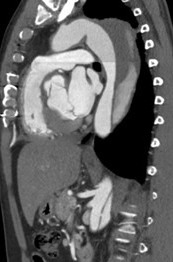

Fig. 1-4: Chronic residual type B dissection after ascending repair. Follow-up CT examination demonstrates TEVAR in descending thoracic aorta extending to the level of the celiac trunk with thrombosis of the false lumen and aortic remodeling due to FLO in false lumen. The FLO is completely collapsed in the FL due to depressurize the false lumen.